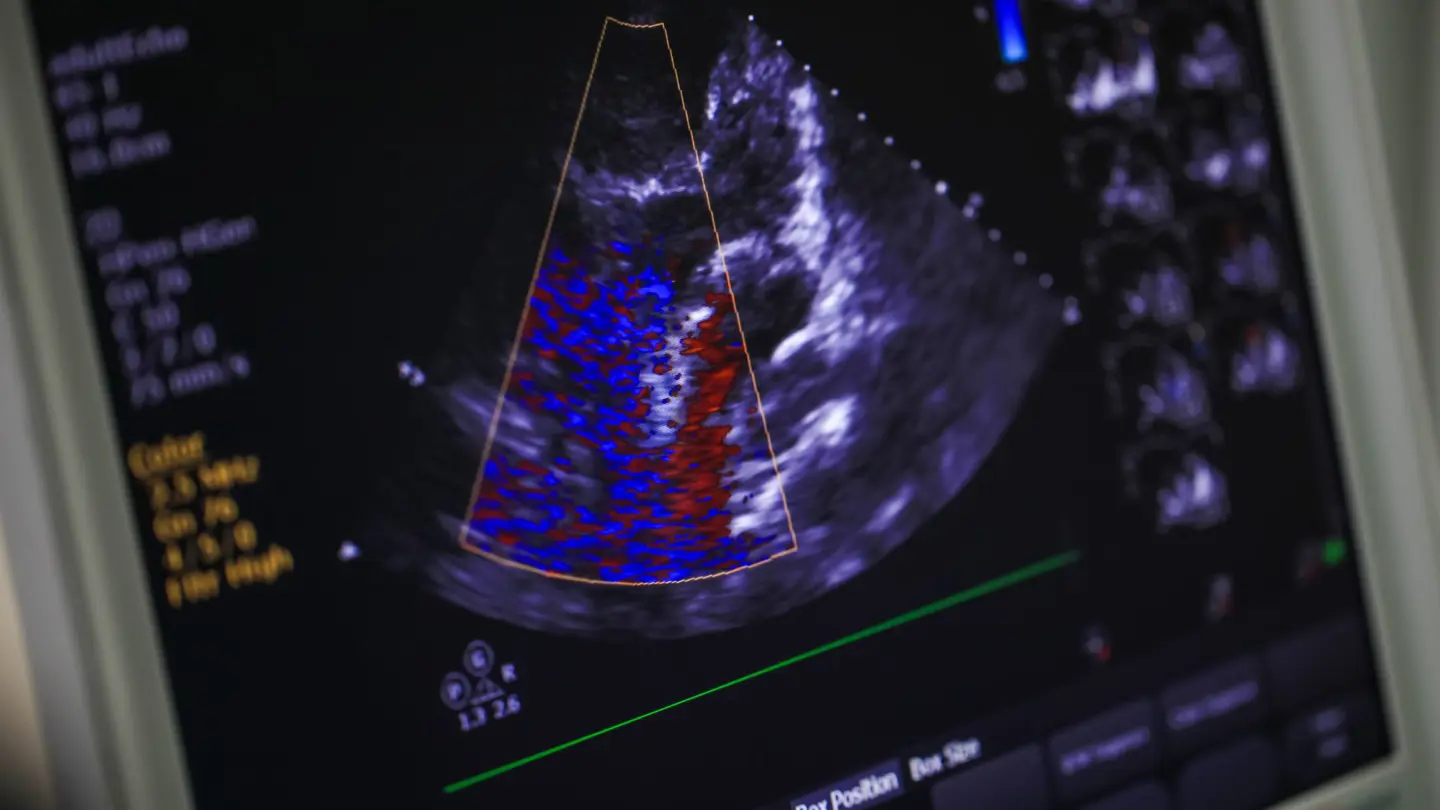

ECHO is short for Echocardiogram, a specialised cardiac ultrasound scan used to assess the structure, condition and function of your heart. It produces images of the heart’s chambers, walls, valves and blood vessels, providing early diagnosis of potential problems.

An echocardiogram - ECHO for short - uses ultrasound waves to produce detailed images of your heart. Fast, painless and non-invasive, it’s the same technology that’s used for pregnancy scans.

Your ECHO scan will show the structure of your heart and nearby blood vessels, and check how blood is flowing. If there’s an infection of the valves (endocarditis), thickened heart walls (cardiomyopathy) or damage to the heart muscles, the ECHO should reveal and gauge the severity of the problem. It can also detect the effects of congenital heart disease.